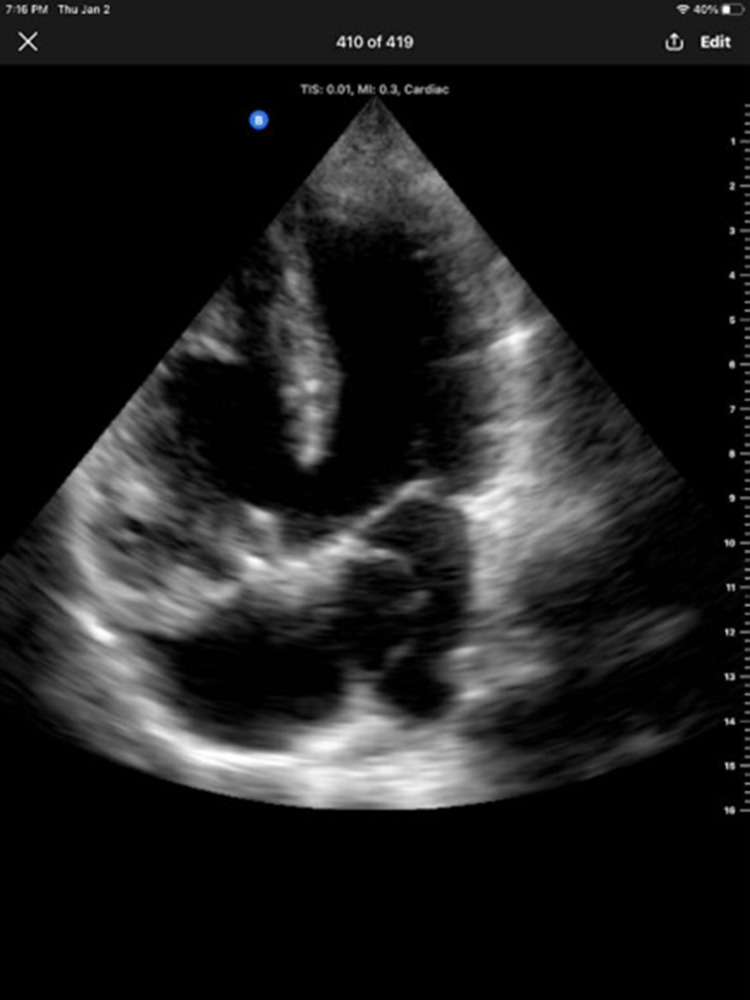

Case report: A 43-year-old male from Somalia presented with recurrent syncope, exertional dyspnea, and a history of congenital heart disease diagnosed in childhood. Due to financial constraints and limited healthcare access, he was unable to undergo surgery. On clinical examination, the patient exhibited cyanosis, grade 3 clubbing, and a pansystolic murmur. Investigations showed secondary polycythemia, right ventricular hypertrophy on ECG, and a large VSD with an overriding aorta. Echocardiography confirmed these findings, revealing the anatomical abnormalities typical of ToF.

Abstract Image